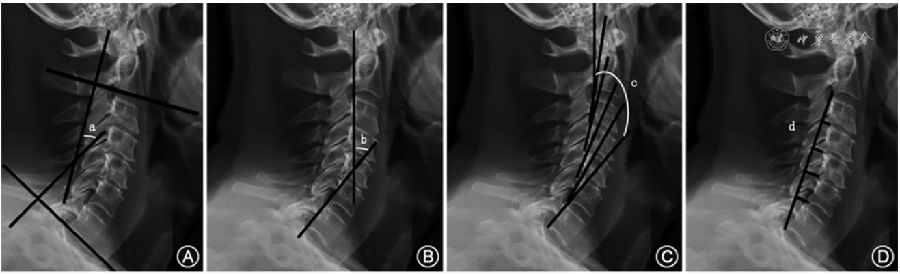

1.CL的测量:测量CL的4种最常见方法包括改良的Cobb方法(mCM)、Jackson生理应力线(JPS)、Harrison后切线(HPT)方法和Ishihara指数(图1A~D)。通过C2法的mCM来获得CL,沿C2和C7下终板绘制两条水平线,分别绘制与前两条线垂直的附加线,两条垂直线所成的角度即C2-7 CL;C1法是从C1的前结节延伸到C1棘突的后缘代替C2的终板作为上参考线来测量C1-7颈椎矢状位Cobb角;用JPS法测量CL时沿C2和C7椎体后壁各画一条直线,这两条直线交角的数值就是CL的测量值。HPT法是从C2到C7所有的颈椎椎体后表面画出平行的直线,然后将所有的节段角度相加得到一个整体的CL角度。Ishihara指数,又称颈椎曲度指数,连接C2的椎体下后端到C7的椎体下后端,从C3、C4、C5、C6椎体下后端分别做垂线,Ishihara指数为4条垂线段的长度和除以C2下后端到C7下后端连线的长度。美国的Janusz等通过对44例患者mCM、JPT和HPT方法的CL测量,认为三种方法均可靠有效,且不同测量者的测量值无明显差异。

(二)颈椎矢状面平衡

矢状面轴向距离(SVA)可以评估全脊柱整体矢状位平衡,颈椎矢状位平衡可以通过CSVA来评估。C2-7 SVA是过C2椎体中心的铅垂线到C7椎体上终板后端之间的距离(图1E)。头部重心(CGH)-C7 SVA(CGH-C7 SVA)是过外耳道前缘的铅垂线到C7椎体后上角的垂线间距离。Iyer等通过双平面成像系统报告了120例无症状患者的C2-7 SVA平均值为21.3 mm,赵文奎等对132名中国无症状成年人测量C2-7 SVA为(18.67±7.96)mm,CGH-C7 SVA为(22.95±12.18)mm。

(三)T1倾斜角

T1倾斜角是T1椎体上终板的延长线与水平线之间的夹角(图1E),T1倾斜角和CL的关系类似于骨盆投射角(PI)和腰椎前凸角(LL)的关系,因为更大的T1倾斜角需要更大的CL来平衡胸部入口和头部的重量。当T1倾斜角在13°~25°时,机体为保持视线水平,可通过上颈椎过伸过屈代偿颈椎的潜在失衡;当T1倾斜角>25°时,颈椎整体容易前倾,重心前移,在重力的作用下,CSVA增大,颈椎曲度发生后凸趋势,导致颈椎矢状位失衡;当T1倾斜角<13°时,存在负平衡。

(四)颈部倾斜角、TIA

TIA是T1椎体上终板中点到胸骨上缘连线和T1椎体上终板垂线之间的夹角(图1E),Lee等认为胸骨、T1肋骨和T1椎体的固定连接导致胸廓入口相对固定,因此,TIA是一个固定的形态学参数。颈部倾斜角是T1椎体上终板中点到胸骨上缘连线与垂直线的夹角(图1E),在无症状的人群中颈部倾斜角保持在44°左右。TIA在数值上等于T1倾斜角和颈部倾斜角相加之和,可以推测较大TIA者为消耗最小能量而获得颈椎水平注视和矢状排列,则需要相应更大的T1倾斜角,进一步CL相应增加。

(五)CBVA

CBVA是一种间接测量水平视线的方法(图1F),可通过临床大体照和X线侧位片上测量患者眉弓到下颌连接线和过眉弓的垂直线对应的角度来获得,当头向下倾斜时,CBVA为正;当头向上倾斜时,CBVA为负;当头部完全竖立并保持中立时,CBVA为零。2016年Iyer等通过对120名无症状成年人进行分析后,其平均CBVA为-1.7°;Song等研究表明CBVA在10°~20°者可获得最佳的结果,可更好地完成室内外活动。

(六)C2PT和SCA

C2PT是C2倾斜角与骨盆倾斜角之和(图1G),C2倾斜角是C2椎体后缘的平行线和垂直方向的夹角,骨盆倾斜角是由S1上终板中点与股骨头中心的连线和铅垂线相交所形成的角度。C2PT角也可测量C2椎体后缘的延长线与股骨头中心到S1上终板中点的连线的延长线夹角。SCA是C7上终板中点和蝶鞍中点连线与C7上终板连线的夹角(图1G),SCA可表示头部前伸姿势,与颈部肌肉能耗密切相关,正常范围为73°~92°。